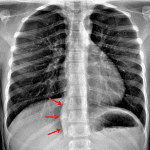

- No focal airspace opacification, pleural effusion, or pneumothorax

- Normal size and configuration of the cardiothymic silhouette

- Right paraspinal fusiform soft tissue density measuring 5 cm in craniocaudal dimension extending from T9-T10 through T12-L1

- Paraspinal mass (ganglioneuroma)

No focal airspace opacification, pleural effusion, or pneumothorax.

Normal size and configuration of the cardiothymic silhouette.

Right paraspinal fusiform soft tissue density measuring 5 cm in craniocaudal dimension extending from T9-T10 through T12-L1 concerning for a neoplasm. Recommend chest CT for further evaluation.